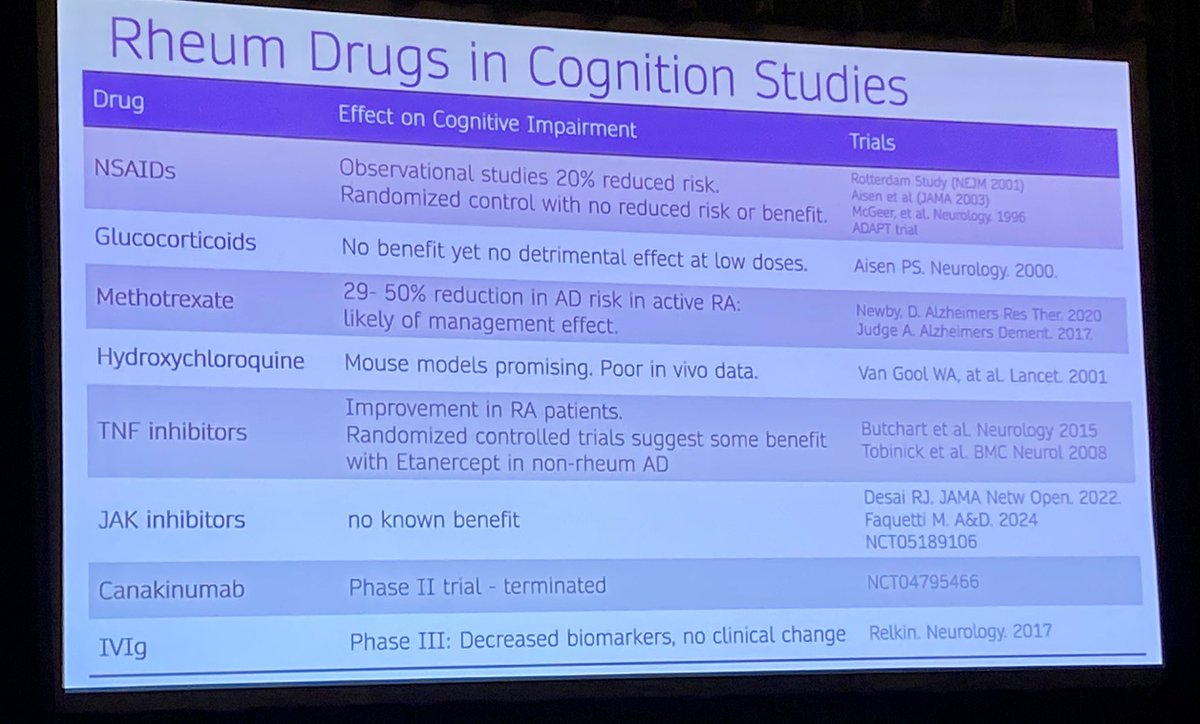

❔Can rheum drugs have beneficial effects on cognition?

💊Possible benefits with MTX and TNFis but certainly an active area of research and more studies needed

#ACR24 @RheumNow https://t.co/lCnIRLwNjK